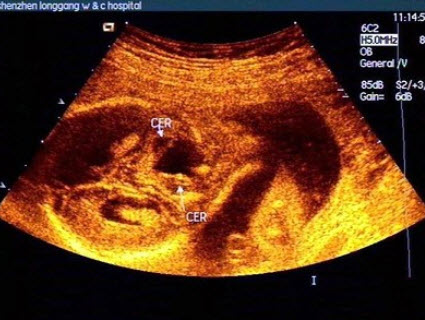

112、单项选择题

胎儿头颅部超声检查如图,最可能的诊断是()